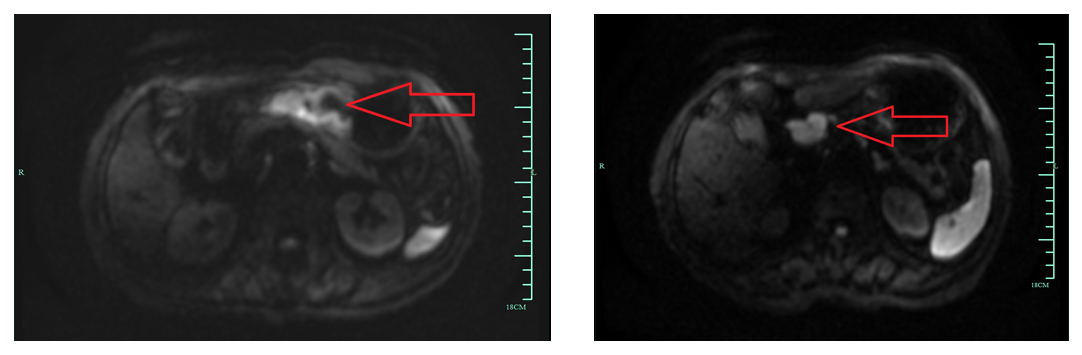

3)2021年7月27日,行胃平扫弥散+增强MRI(图2)示:胃角、胃窦部肿瘤病灶累及范围约7.5 cm;Borrmann分型:Ⅲ型(溃疡浸润型);浸润深度:累及浆膜下层;区域及远处淋巴结转移:有,胃小弯侧及胃窦部周围见多发肿大淋巴结影,DWI为高信号,强化不均。

图2 基线胃平扫弥散+增强MRI